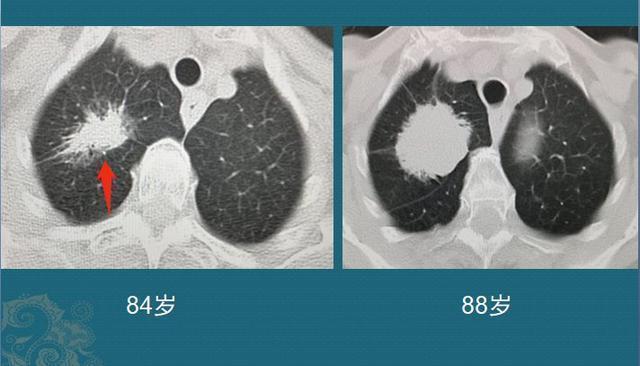

现在治疗肺结节的各种秘方比较多,有的病人不信任医生,或者是不方便细说的家庭原因,最终会放弃早期手术机会,有时挺叫人无奈的。当然,还有一部分是属于高龄病人,担心身体虚弱,扛不过手术关,选择保守治疗或者随访观察为主,有些生长缓慢的也比较幸运:

文章插图

这位老人84岁,因为咳嗽、胸闷查出混合磨玻璃结节,形态不规则,边缘有清晰的磨玻璃影,同时伴有胸膜牵拉,是典型肺腺癌的特点。但她比较幸运,癌细胞增殖速度不快,今年已经88了,精神头还不错!小结:混合磨玻璃结节可以由纯磨玻璃结节发展而来,逐渐增大,也可以逐渐变成实性结节。这个进展过程也是因人而异,不是固定的。3.实性肺结节这种类型的相对比较少,但往往生长速度更快,要更加重视!